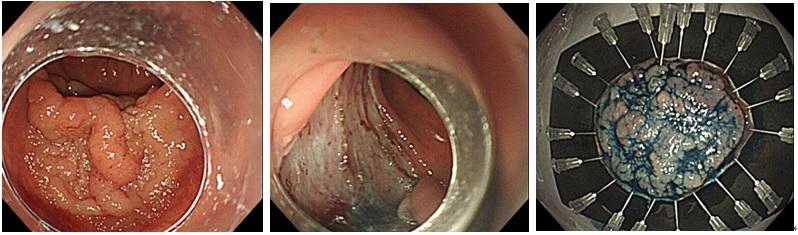

大腸ポリープ切除術(EMR、コールドポリペクトミー)

EMRは従来から広く行われている治療法です。ポリープ直下に生理食塩水を注入し、「スネア」と呼ばれる金属製の輪をかけて高周波電流によって切り取ります。主に20mm以下のポリープに対して行います。

一方でコールドポリペクトミーとは比較的新しい治療法であり、スネアのみを用いて電流を使わずにポリープを切り取る方法です。電流による血管への余計なダメージがないことでEMRよりも術後出血が少ないと言われており、主に小さめの良性ポリープに対して行います。

大腸腺腫に対するコールドポリペクトミー

出血性胃潰瘍に対する凝固止血

大腸憩室出血に対するEBL(バンド結紮術)